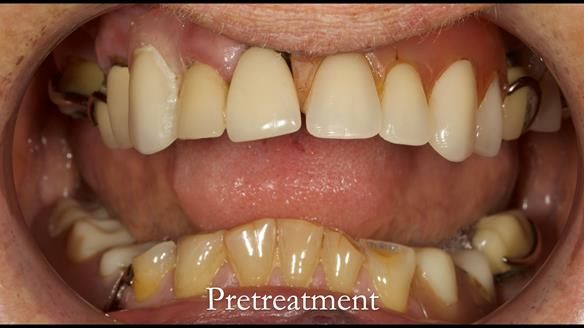

Aesthetically and functionally poor RPDs were replaced for Eileen, a 74 year old woman.

- Upper and lower metal based RPDs, poorly fitting, worn occlusal surface, reverse curve aesthetics, lacking support

- Poor dental appearance with reverse incisal curve

- The upper right central and lateral incisors with post crowns. Healthy and functionally secure but with poor appearance, contributing to the reverse curve.

- Moderate to heavily restored dentition with deep overbite (Class 2 div II)

- Yellowish lower front teeth with small amount of wear.

- The lower right canine (LR3) is worn with MOD cavity.